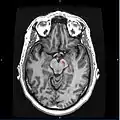

توده سیاه (Substantia nigra) بخشی از میانمغز و دارای نورونهایی است که در ارتباط با عقدههای قاعدهای در تنظیم حرکات نقش دارند. زوال نورونهای دوپامینرژیک این عقده عامل اصلی بیماری پارکینسون است.[1]

![]() Coronal slices of human brain showing the عقدههای قاعدهای، globus pallidus: external segment (GPe), subthalamic nucleus (STN), globus pallidus: internal segment (GPi), and substantia nigra (SN, red). The right section is the deeper one, closer to the back of the head. | |